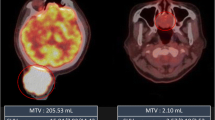

Representative 18F-FDG-PET images of three patients are shown in Fig. 6. As shown in the cases from the left to the right, the Ki-67 expression, SUVmax, and TLG increased, whereas the MTV showed a different tendency.

18F-FDG-PET images (early phase) of three representative patients with soft-tissue sarcomas. a Synovial sarcoma image with relatively low Ki-67 expression. b Pleomorphic undifferentiated sarcoma image with moderate Ki-67 expression. c Dedifferentiated liposarcoma image with high Ki-67 expression. Among them, the Ki-67 expression, SUVmax, and TLG values showed the same tendency, whereas the MTV did not